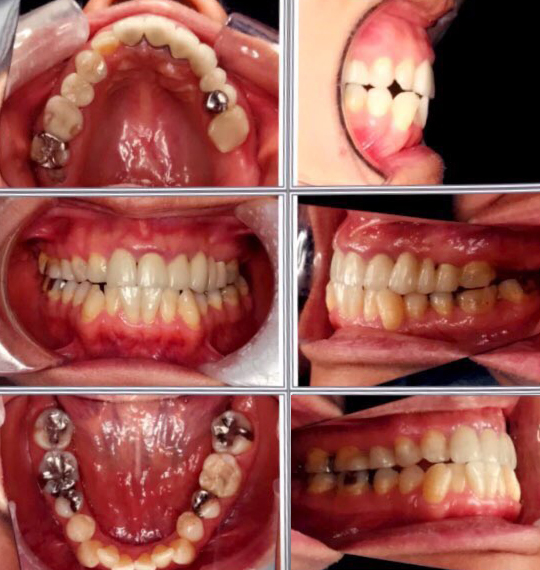

切端唆合を治し、正中線を合わせ、下の歯並びもきれい 体にとって健康な噛み合せにしたい

左上1」2」3、4、5」のブリッジのうち、この写真撮影後に2番を抜歯したため、現在2、3、4は欠損して、今は仮の入歯が入っています。

左上1番と5番は神経が無く、7番と8番は欠損です。

20年前に、左上1〜5番のブリッジの土台を作った医師に、噛み合せが合っていないことを指摘されました。

【矯正に期待すること】切端唆合を治し、正中線を合わせ、下の歯並びもきれいにする。体にとって健康な噛み合せにしたい。

写真で見た限りでは、上顎前歯に比較して、下前歯のサイズが大きく切端咬合になっている様です

一般的に、矯正だけで切端咬合を治すためには、最小限、右側第一小臼歯(糸切り歯の後ろの歯)1本の抜歯か、下前歯を削って小さくする必要があります。